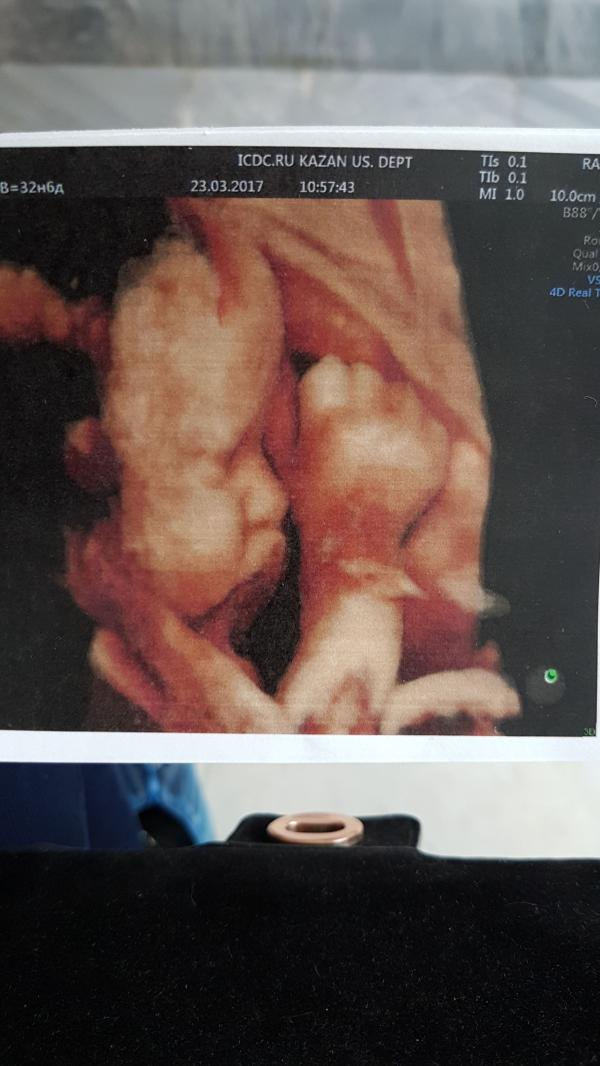

Моя маленькая бука😉щечки и писюня мамины,а все остальное папино😎 даже стопка и та большая))) папина защитница растет😙 так долго ждала этого дня,чтоб наконец увидеть свою девочку💋🌸🌸🌸

Какая она хорошенькая, тьфу тьфу😍 а сколько вам тут неделек?☺️

@guliyag да,я сама удивлена,что такой удачный кадр сняли) учитывая,что все время на узи она танцы устроила😂😙

Такое фото удачное👍🏼👍🏼щёчки то щечки😍у моей на всех ужи тоже губки бантиком и щёчки надутые были)) такая же и родилась щекастая)